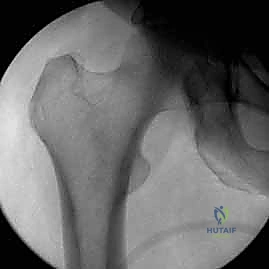

- الأشعة السينية (X-Rays): أخذ صور من زوايا متعددة (أمامي خلفي، وجانبي) لتحديد موقع الكسر ونوعه.

- الأشعة المقطعية (CT Scan): وهي ضرورية جداً في كسور عظم الفخذ البعيدة، خاصة إذا كان الكسر يمتد إلى داخل مفصل الركبة (Intra-articular fractures). تساعد الأشعة المقطعية الدكتور هطيف على بناء نموذج ثلاثي الأبعاد للكسر، مما يسهل التخطيط الجراحي وتحديد أماكن وضع المسامير بدقة.